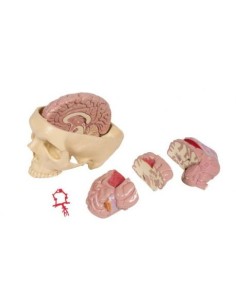

Découvrez le monde de l'anatomie avec des modèles anatomiques de précision

Bienvenue sur Tuttoanatomia.it, le portail de référence en Italie pour l'achat de modèles anatomiques, de posters, de lits portables, de simulateurs médicaux et de littérature spécialisée. Grâce à nos modèles anatomiques de pointe de 3B Scientific et Erler Zimmer, nous offrons une expérience d'apprentissage inégalée.

Des modèles anatomiques détaillés pour tous les besoins

Du crâne en 22 parties à verrouillage magnétique aux modèles de colonne vertébrale, des modèles d'articulation aux modèles de cœur, chaque pièce de notre collection est conçue pour une immersion totale dans l'étude de l'anatomie humaine. Nos modèles, réalisés à partir de scans d'os réels, garantissent une expérience tactile authentique et une fidélité de poids presque identique aux originaux.

Indispensables aux étudiants comme aux professionnels, nos modèles anatomiques sont des outils pédagogiques qui permettent d'observer les structures anatomiques avec précision, en évitant les dissections ou les études invasives. Ils sont également utiles pour expliquer les pathologies aux patients, ce qui rend la communication plus efficace et permet de gagner un temps précieux.